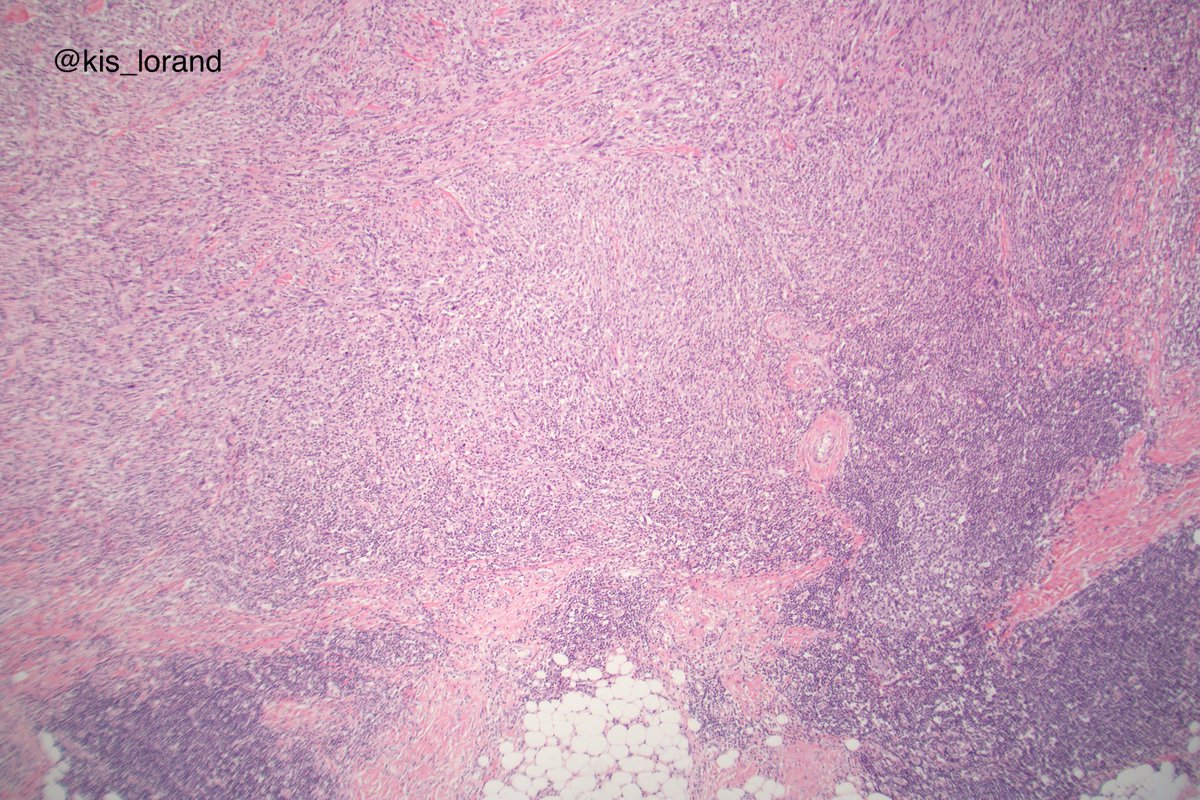

2. The pictures show an intradermal, well circumscribed cellular lesion without a junctional component, surrounded by lymphoid aggregates. The high power pictures shows clear cut atypia. Mitoses were present but not shown in the pictures. The IHCs favour a melanocytic tumor (

3. (the homogenous S100 and Sox10 also favours melanoma over MPNST that show focal, week labeling for these markers).

So the diagnosis is an invasive melanoma, spindle cell or desmoplastic probably of less importance from the point of view of the patients management. Even so...

4. the tumor is too cellular for a desmoplastic melanoma (DM); DM is a pink lesion on low power, looks like a scar; the neoplastic cells are infiltrating a dense fibrous stroma.

DM is a better defined entity while spindle cell melanoma is a more heterogeneous entity.